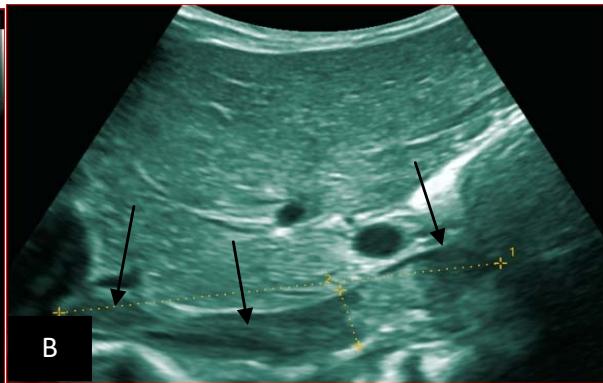

Figure 5: Abdominopelvic ultrasound control after 6 courses of chemotherapy in the same 3 year old patient with a ruptured left renal nephroblastoma; Images A, F, G, and H: show regression of the solid, endo and exo renal, left nephroblastoma mass treated with 6 courses of chemotherapy (current volume 430 ml vs) Images: B, C, and: show persistence of thrombotic permeation pan vena cava and ipsilateral renal. Image E: shows a volumetric regression of the intra-lesional hematic collection, at the tumor rupture estimated at 34.49 ml VS, Image I: represents the right kidney in B mode which is of normal echoculture. Source: Dr. Frederick Tshibasu Tshienda database.